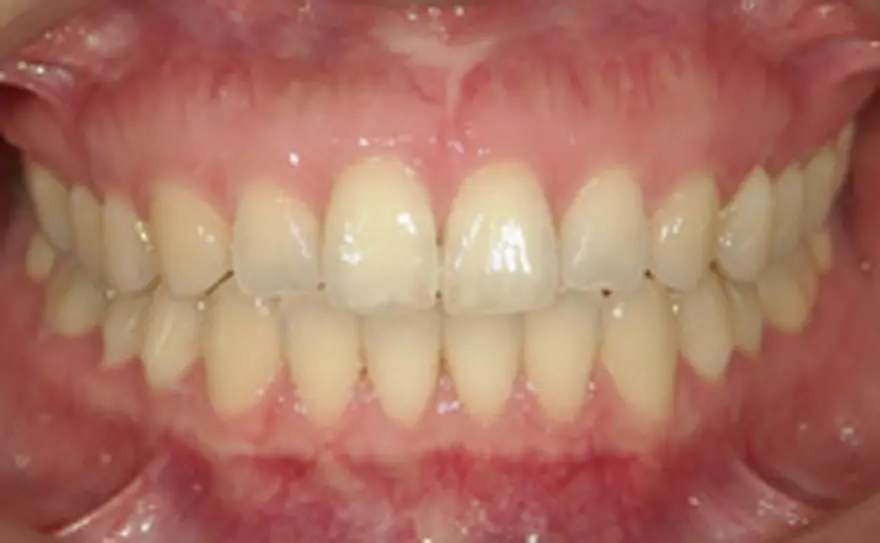

MTM(部分的な矯正)治療例4

矮小歯のあるケース

| 患者さまの年齢・性別 | 20代・男性 |

|---|---|

| 治療期間 | 5ヵ月 |

| 治療費(税込) | 242,000円 |

| 主訴 | 前歯の隙間が気になる。 |

| 診断名・主な症状 | 真ん中のスペースの閉鎖と右の矮小歯が裏側になってしまっている。 |

| 治療に用いた主な装置 | セルフライゲーションブラケット装置(デイモンシステム) |

| 治療内容 | 前歯の隙間を閉じ、右の裏側にある歯を前方に移動させています。上顎左右の前歯の隣の歯が矮小歯と言う本来より小さい歯のため、このままでは再度隙間があいてくる可能性があります。矯正治療後、この歯を少し大きくする治療が必要となります。 |

| 抜歯部位 | 非抜歯 |

| 通院回数・メンテナンス頻度 | 5回 |